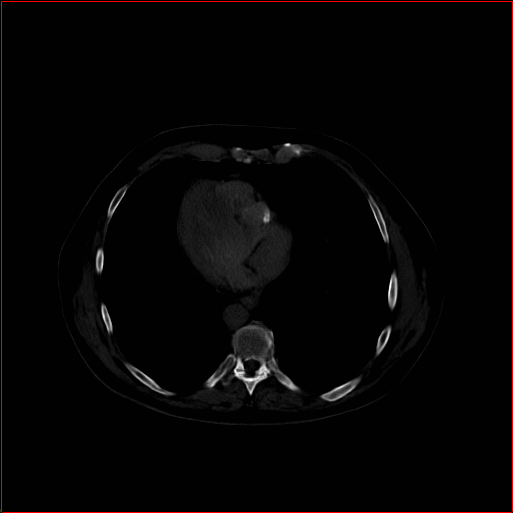

MAISI-v2 Controlnet qualitative Results:

Figure 5 shows qualitative results for MAISI-v2 Controlnet on 5 types of tumors.

Lung Tumor

0.75×0.75×0.60.75\times 0.75\times 0.6

mm

512×512×512512\times 512\times 512

Liver Tumor

0.75×0.75×0.50.75\times 0.75\times 0.5

512×512×768512\times 512\times 768

Panc. Tumor

1×1×11\times 1\times 1

Colon Tumor

0.75×0.75×1.50.75\times 0.75\times 1.5

512×512×256512\times 512\times 256

Bone-Les

1×1×1.31\times 1\times 1.3

512×512×384512\times 512\times 384

Figure 5: MAISI-v2 segmentation-guided results for five types of tumors. We show results for different voxel spacing and volume size to demonstrate the flexibility of MAISI-v2. Different Hounsfield Unit window is used to better show the contrast between tumor and normal tissues.